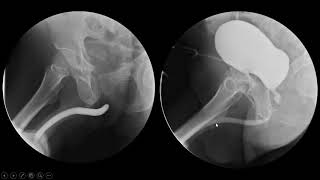

WebA estenose de junção uretero-pélvica (JUP), também chamada de obstrução da junção pieloureteral, é uma obstrução do trato urinário, onde um pedaço do ureter, o canal que. WebO ureter é uma estrutura fina e comprida que mede de 25 a 30 cm e transporta a urina do rim até a bexiga, e não tem relação com a uretra. A uretra do. Web“Estenose” é um termo médico genérico utilizado para designar qualquer tipo de estreitamento capaz de afetar o corpo humano. A estenose espinhal pode acontecer sem. WebEstenose uretral é um estreitamento de um segmento da uretra, que pode resultar em diminuição ou mesmo interrupção completa do fluxo urinário, acarretando em uma série. WebA estenose de uretra é um estreitamento da uretra, que é a porção do trato urinário que comunica a bexiga ao exterior do seu corpo e serve de passagem para a urina. A. WebA estenose uretral é uma doença que causa o estreitamento da uretra e a diminuição do fluxo de urina a partir da bexiga para o exterior. INDICE Causas Sintomas Diagnóstico. WebA estenose uretral é uma condição médica que afeta principalmente os homens e consiste no estreitamento da uretra — canal responsável por transportar. WebEstenose uretral é um estreitamento de um segmento da uretra, que pode resultar em diminuição ou mesmo interrupção completa do fluxo urinário, acarretando em uma série.

WebA estenose uretral é uma condição médica que afeta principalmente os homens e consiste no estreitamento da uretra — canal responsável por transportar. WebEstenose uretral é um estreitamento de um segmento da uretra, que pode resultar em diminuição ou mesmo interrupção completa do fluxo urinário, acarretando em uma série.